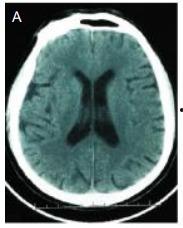

首先,得给你解释一下什么是图脑技术。简单来说,图脑技术就是利用计算机图形学、人工智能和神经科学等领域的知识,将大脑的结构和功能以图形化的方式呈现出来。这样一来,我们就能更直观地了解大脑的运作原理。

2. 精神疾病诊断:图脑技术可以帮助医生更准确地诊断精神疾病,如抑郁症、焦虑症等。